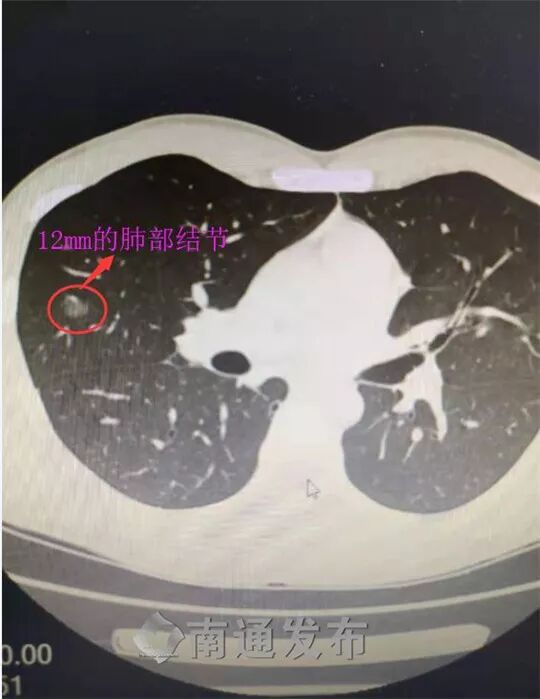

入职体检无意查出两肺结节,最大的12mm

小伙子说,行!CT扫描结果让医生都紧张,小伙子两肺都有结节,其中右中肺上的结节有12mm。

根据形态观察,医生怀疑“肺癌可能”,这让他顿觉“怀疑人生”。